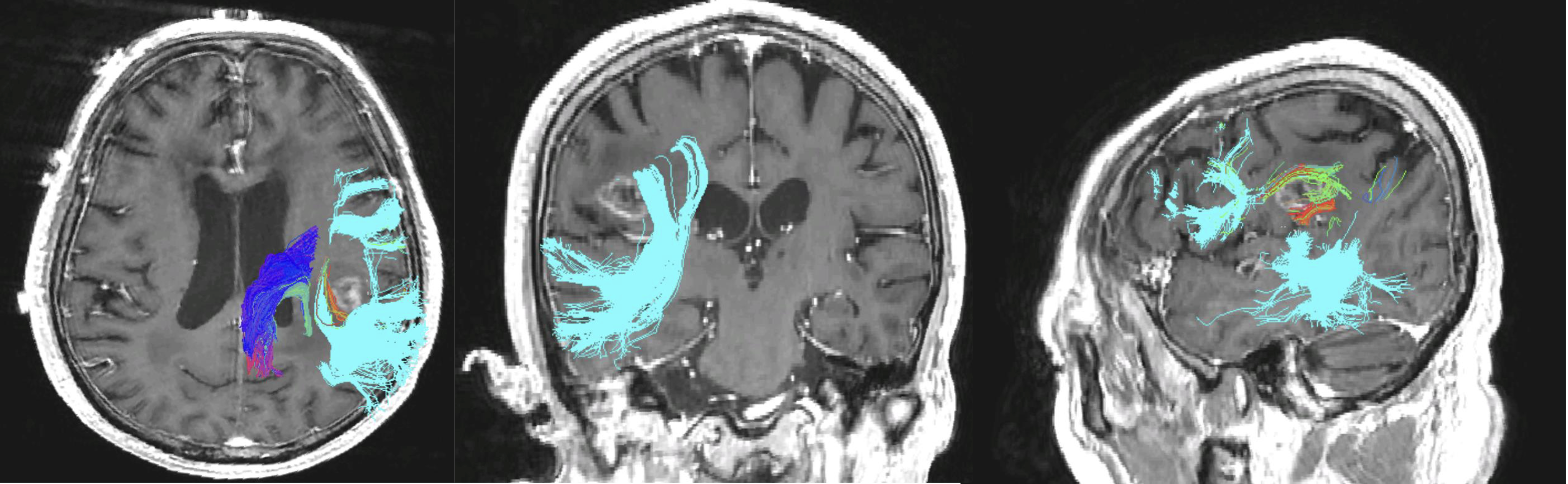

Vanitha Sankaranarayanan stood in awe, dressed head-to-toe in sterile scrubs, in the operating room. She observed as a neurosurgeon performed brain surgery guided by critical information from a diffusion tenser imaging (DTI) brain scan displayed on a digital screen. Through sensors on the patient’s physical brain, the surgeon could see the brain’s essential motor pathways colorfully illuminated on-screen, and where they were in relation to the tumor and how best to avoid them during surgery.

Observing this surgery shortly after she joined UCSF’s 3DLab in 2009 has influenced her work ever since. This experience gave her an opportunity to see how DTI tractography – the eloquent neuronal pathways she was hired to create through post-processing of MRI images – were being used in a neurosurgical procedure.

In the beginning, Sankaranarayanan’s work focused on interior brain tractography of motor pathways. Then neurosurgeons requested to see optic and language pathways too, which Sankaranarayanan now includes, using the same DTI techniques that involve seeding a region of interest on the MRI, and then working with an algorithm to generate the pathways. Advances in technology and computing power have dramatically reduced the processing time for brain tractography, increasingly used when tumors are located close to motor, optic, and language pathways. Now, DTI imaging is also being used for arteriovenous malformation (AVM) and epilepsy pre-op cases.